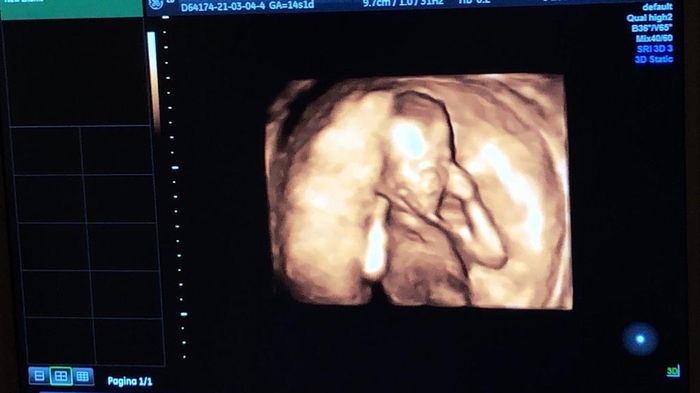

Future mamme Agosto 2021!

Da Rosanna , Il 4 Marzo 2021 alle 15:41

Ciao a tutte! ...